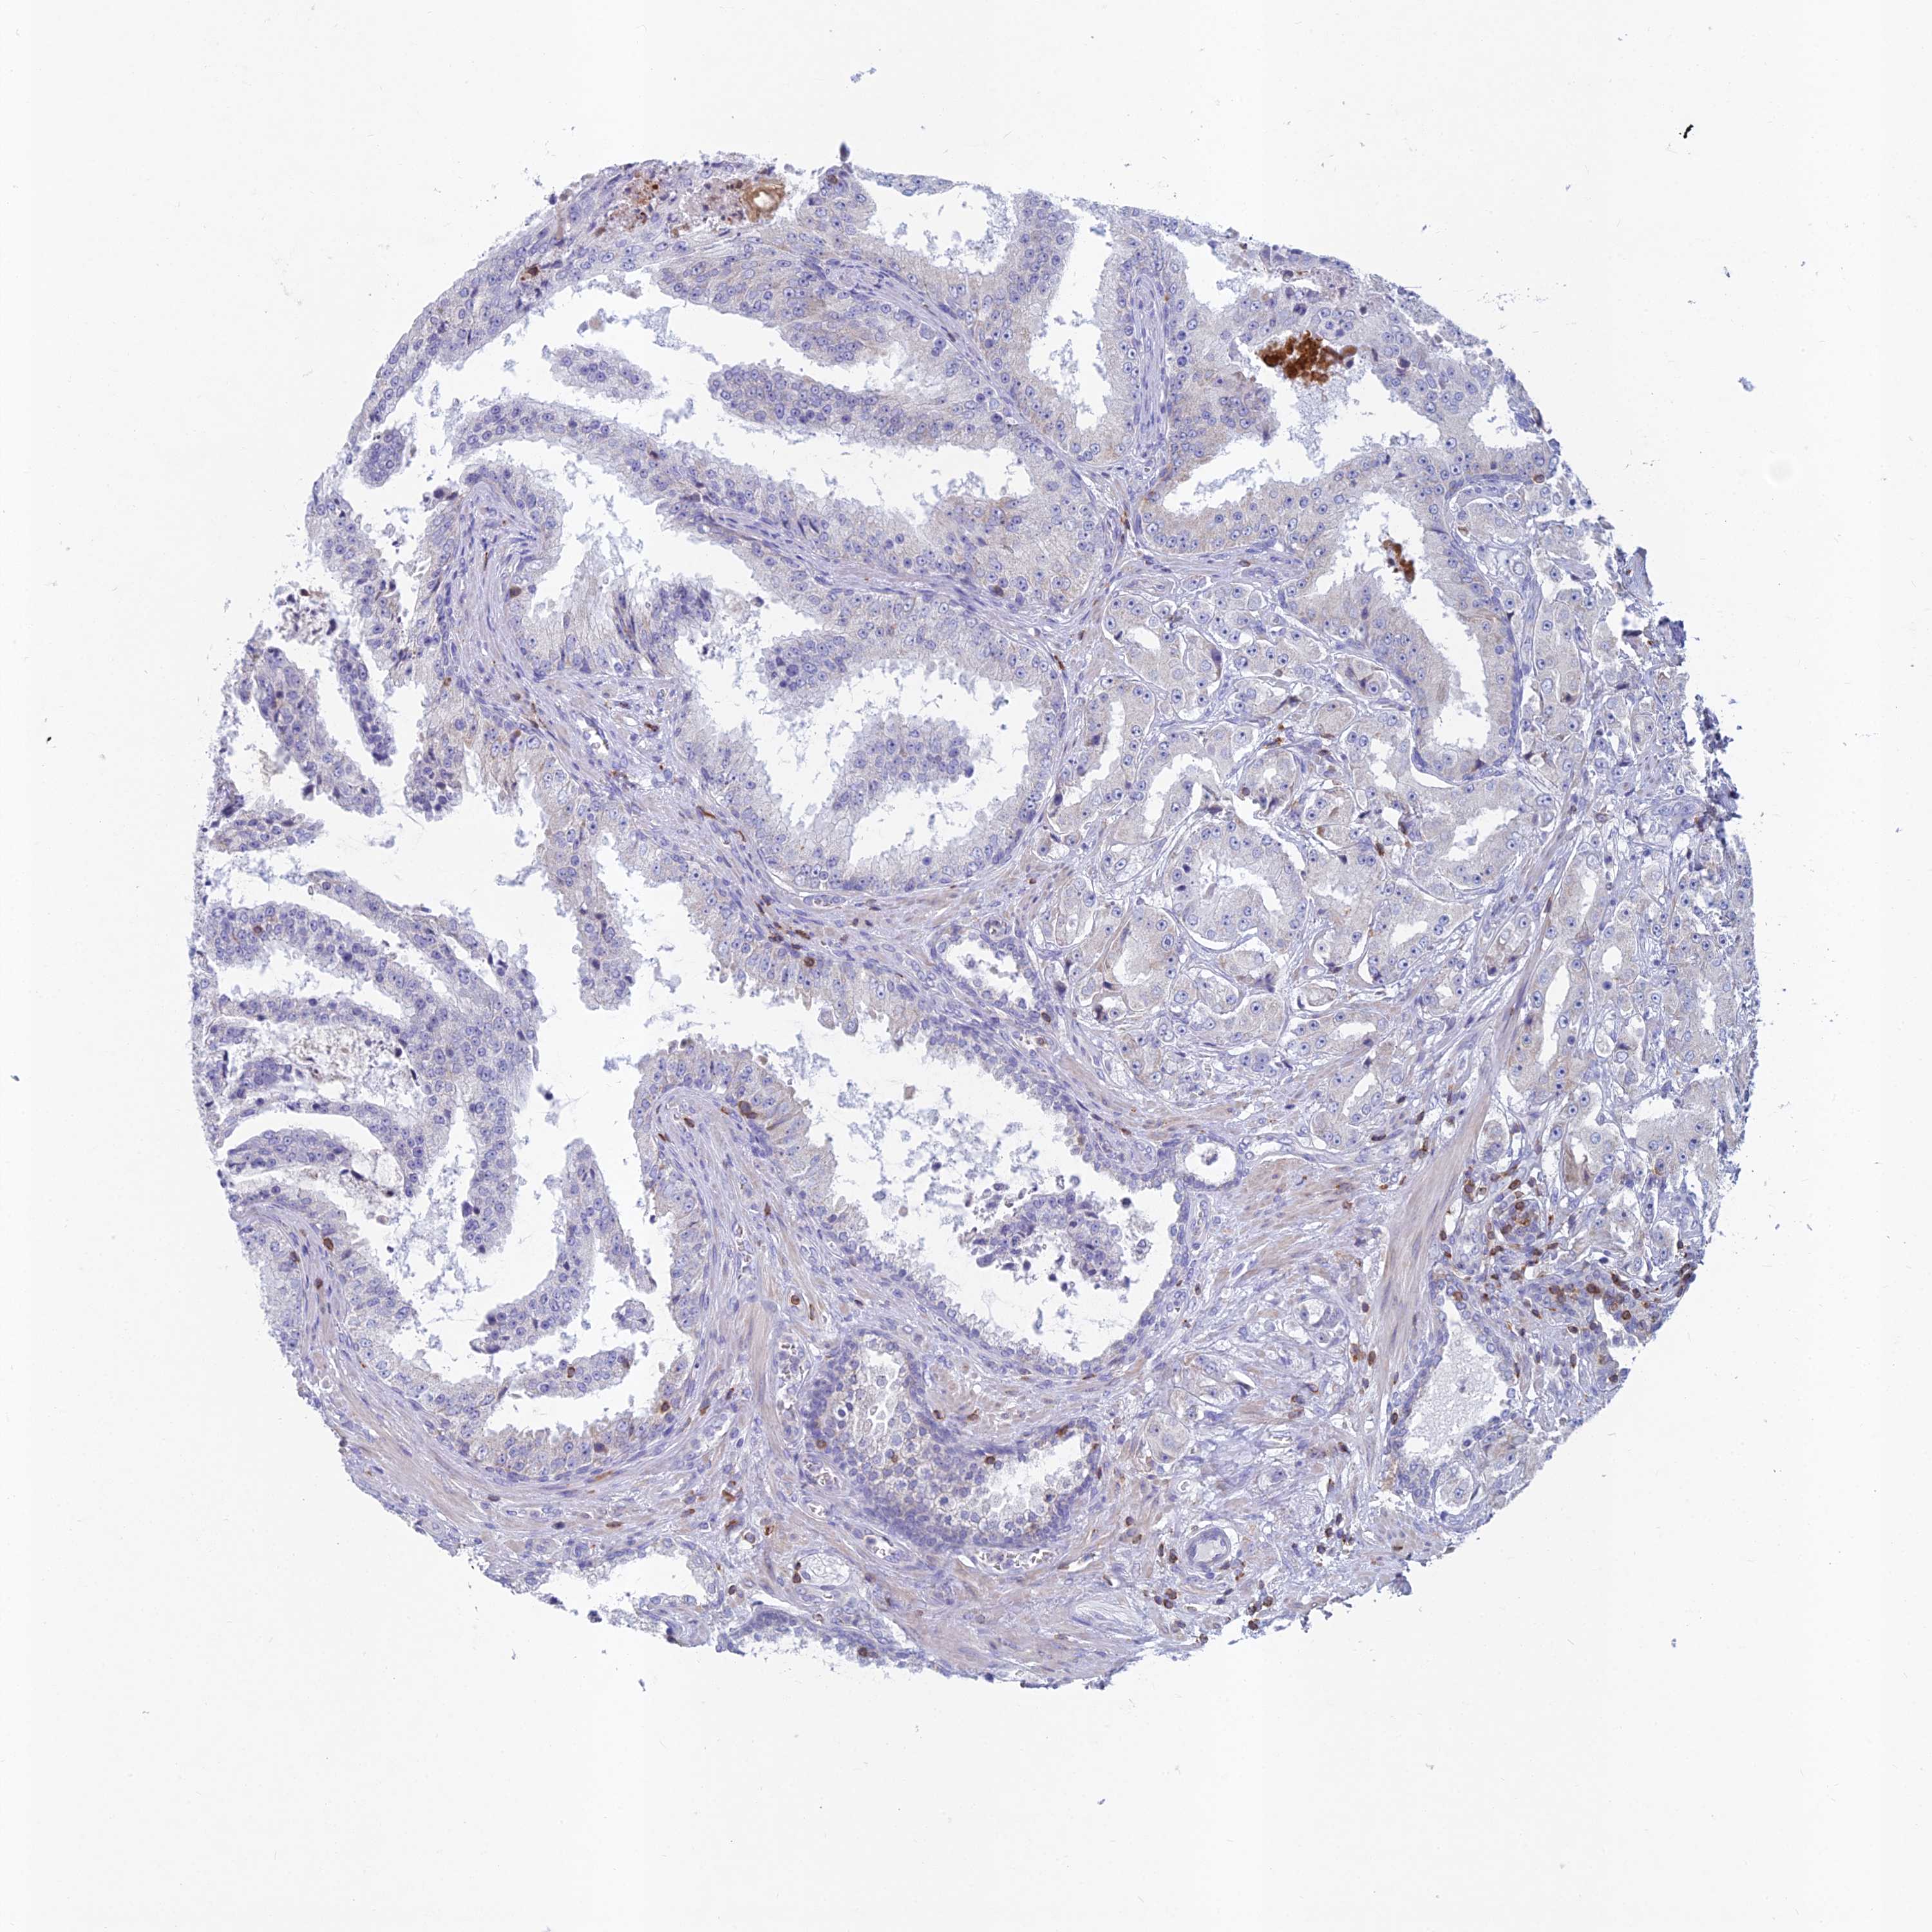

PROSTATE CANCER - Protein expressioni

A mouse-over function shows sample information and annotation data. Click on an image to view it in a full screen mode. Samples can be filtered based on level of antibody staining by selecting one or several of the following categories: high, medium, low and not detected. The assay and annotation is described here.

Note that samples used for immunohistochemistry by the Human Protein Atlas do not correspond to samples in the TCGA dataset.

Antibody stainingi

Antibody staining in the annotated cell types in the current human tissue is reported as not detected, low, medium, or high, based on conventional immunohistochemistry profiling in selected tissues. This score is based on the combination of the staining intensity and fraction of stained cells.

Each image is clickable and will lead to virtual microscopy that enables deeper exploration of all samples and also displays staining intensity scores, fraction scores and subcellular localization as well as patient and tissue information for each sample.

Antibody HPA044127

Staining

High

Medium

Low

Not detected

Intensity

Strong

Moderate

Weak

Negative

Quantity

>75%

75%-25%

<25%

None

Location

Nuclear

Cytoplasmic/membranous

Cytoplasmic/membranous,nuclear

Adenocarcinoma, High grade

Adenocarcinoma, Low grade